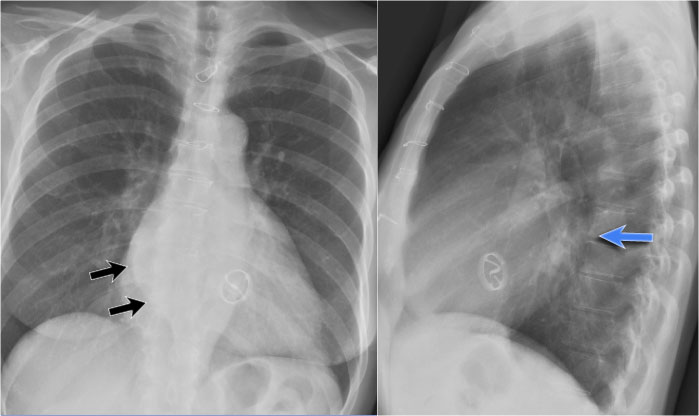

Left Atrial Enlargement

• Patient with a history of chronic mitral valve disease and valve replacement.

• Extreme dilation of the LA leads to bulging of both the right upper cardiac contour (black arrows) and posterior heart border on lateral view (blue arrow).

Right Ventricular Enlargement

First study the PA and lateral chest film and then continue reading.

Findings

• Chest radiographs show massive cardiomegaly, predominantly due to right ventricular dilation (yellow arrow on lateral view).

• Small aortic knob (blue arrow), with dilation of the pulmonary trunk and right lower pulmonary artery.

• Findings suggest a left-to-right shunt with secondary pulmonary hypertension.